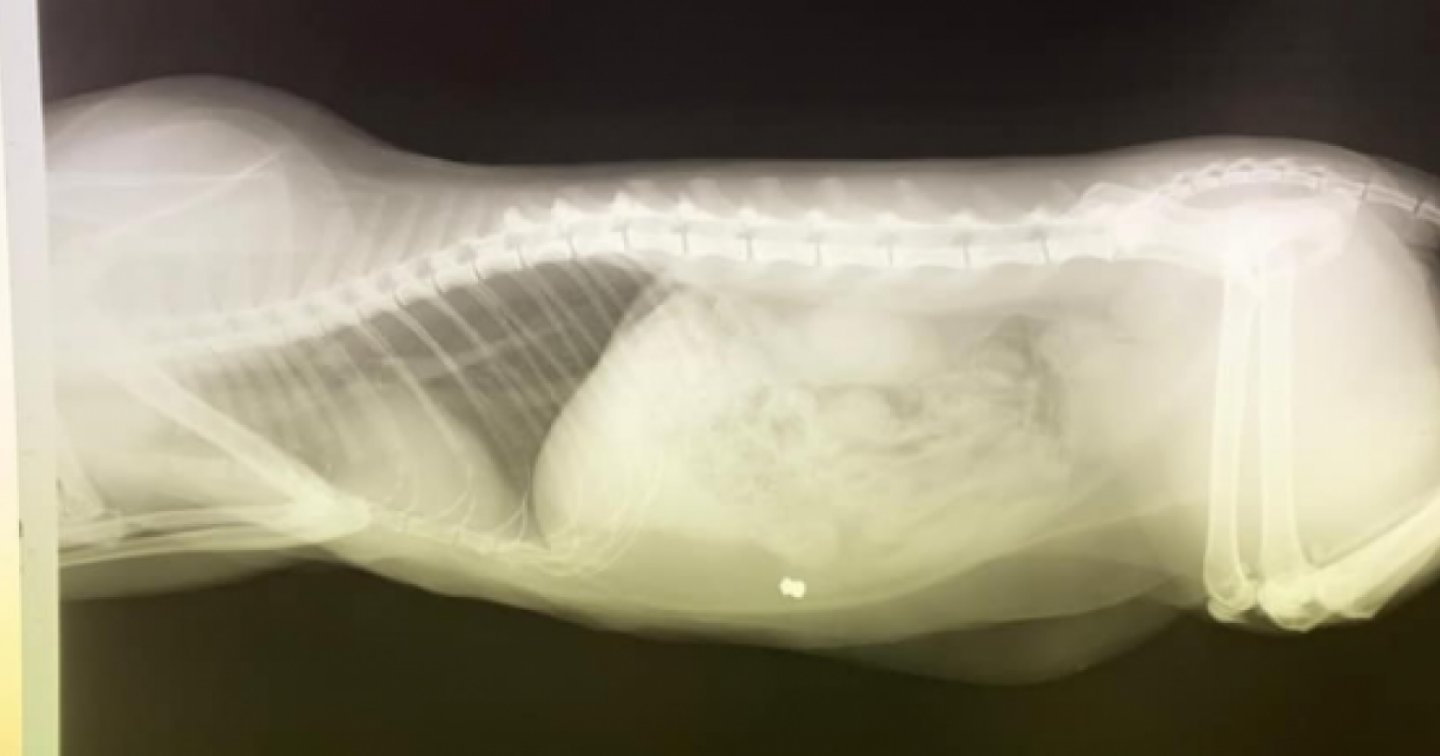

ROBASACCO – "Schifo, siamo nel 2020 e c'è gente che si diverte – probabilmente per gioco – a sparare agli animali". Inizia così il post Facebook con cui Adela denuncia quanto accaduto la prima notte dell'anno al suo gatto a Robasacco. "In questo caso – scrive postando la radiografia del corpo del gattino – è coinvolto il mio gatto. Giuro che se becco chi è stato, non so cosa potrei fargli. Sei un bastardo".

"Tutto questo – continua – è successo a Robasacco. Fate attenzione, perché oltre ai bocconi avvelenati, ora bisogna fare attenzione anche ai proiettili di gomma". Una vicenda che ha suscitato parecchia indignazione sui social, dove spicca la presa di posizione del deputato PPD Giorgio Fonio.